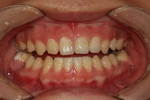

| ¾Õ´Ï ÃæÄ¡ |

| ¾Õ´Ï ÃæÄ¡°¡ ÀÖ¾î¿ä |